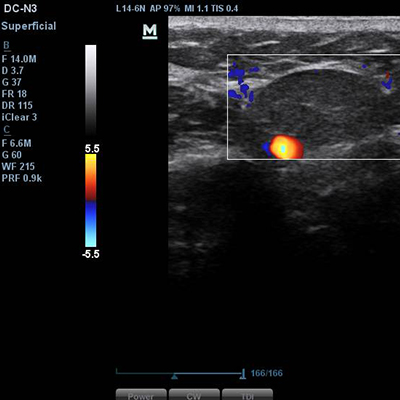

[이물질제거] 17.01.31 - 이물질제거 - 전후사진

17.01.31 - 이물질제거 - 전후사진